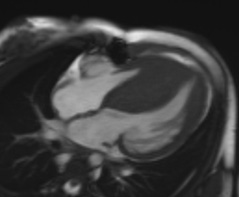

Description: There are many types of heart muscle problems that can affect children. Cardiomyopathies are due to genetic, or inherited, conditions that can cause the heart chambers to become enlarged, the heart muscle to thicken, or other changes with the muscle. Myocarditis can cause damage to the heart muscle after an infection.

Why MRI: Heart MRI is used to capture pictures of the heart chambers and muscle to help figure out the type of heart muscle problem that a child has or if there are changes over time. It is also used to measure how well the heart is pumping. Sometimes Heart MRI will be used to look for any scar or damaged areas.

Images: DCM, HCM, LGE, T1/T2 map